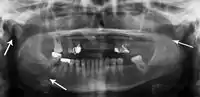

Panoramic radiography

Panoramic radiographs are tomograms where the mandible is in the focal trough and show a flat image of the mandible. Because the curve of the mandible appears in a 2-dimensional image, fractures are easier to spot leading to an accuracy similar to CT except in the condyle region. In addition, broken, missing or malaligned teeth can often be appreciated on a panoramic image which is frequently lost in plain films. Medial/lateral displacement of the fracture segments and especially the condyle are difficult to gauge so the view is sometimes augmented with plain film radiography or computed tomography for more complex mandible fractures.

Research has shown that panoramic radiography is similar to computed tomography in its diagnostic accuracy for mandible fractures and both are more accurate than plain film radiograph.[12] The indications to use CT for mandible fracture vary by region, but it does not seem to add to diagnosis or treatment planning except for comminuted or avulsive type fractures,[13] although, there is better clinician agreement on the location and absence of fractures with CT compared to panoramic radiography.[14]

Panoramic radiograph of a simple mandible fracture of the right mandibular body, minimally displaced. Note that the teeth to the left of the fracture do not touch